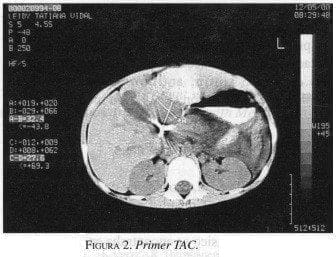

La tomografía axial computarizada (TAC) abdominal (figura 2) reveló una lesión intrahepática de baja atenuación, sólida, hacia el hilio hepático, mal definida y de 3,2 x 2,7 cm, con gran dilatación de las vías biliares intra y extrahepáticas.